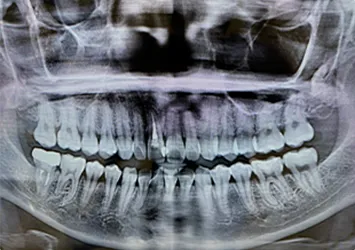

1 歯科用CTなどを活用した正確な診査診断

インプラント治療成功のポイントは「口腔衛生環境」、「身体の健康状態」、「骨の状態(骨の幅、深さ、密度)」、「インプラントの埋入位置」、「担当するスタッフの技術や評判」、「院内の衛生環境」等様々あります。

当院では、歯科用CTによる一般的なレントゲン写真よりも高い精度での検査により、患者様の顎の状態を詳細に把握することで、手術の成功率を高めるとともに患者様の治療時と治療後の痛みの軽減にも役立ちます。

歯科用CT 恵比寿南DENTAL

歯科用CT

歯科用CTは、従来の2次元のレントゲン装置とは異なり、3次元の立体画像を撮影可能にする装置で、精度の高い診査診断検査や精密歯科治療を行う際には欠かせない機器です。

従来の2次元のレントゲン撮影による画像では見ることができない口腔内を3次元的に把握できることで、歯や歯周組織、顎の骨やその中にある神経や血管の位置まで正確に把握することができます。

当院では、歯科用CTを完備しておりますので、歯周病治療、根管治療、インプラント治療や親知らずの抜歯など、精度の高い診査診断が求められる治療も安全に受けて頂けます。